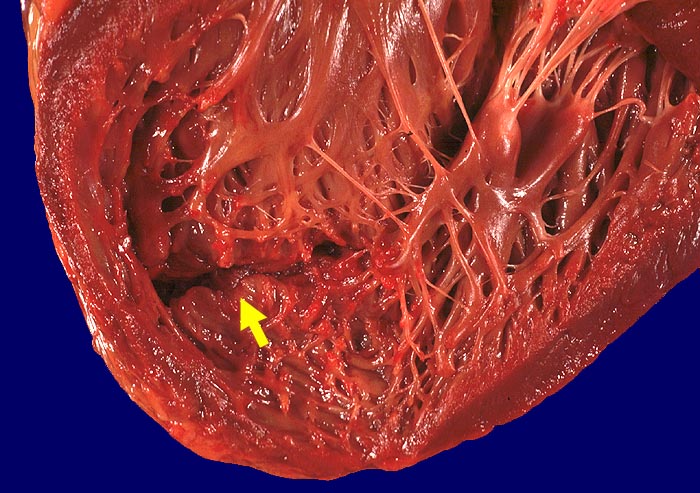

AP/ Akuter Myokardinfarkt

Akuter Myokardinfarkt

Makroskopie

Pathologischer Befund